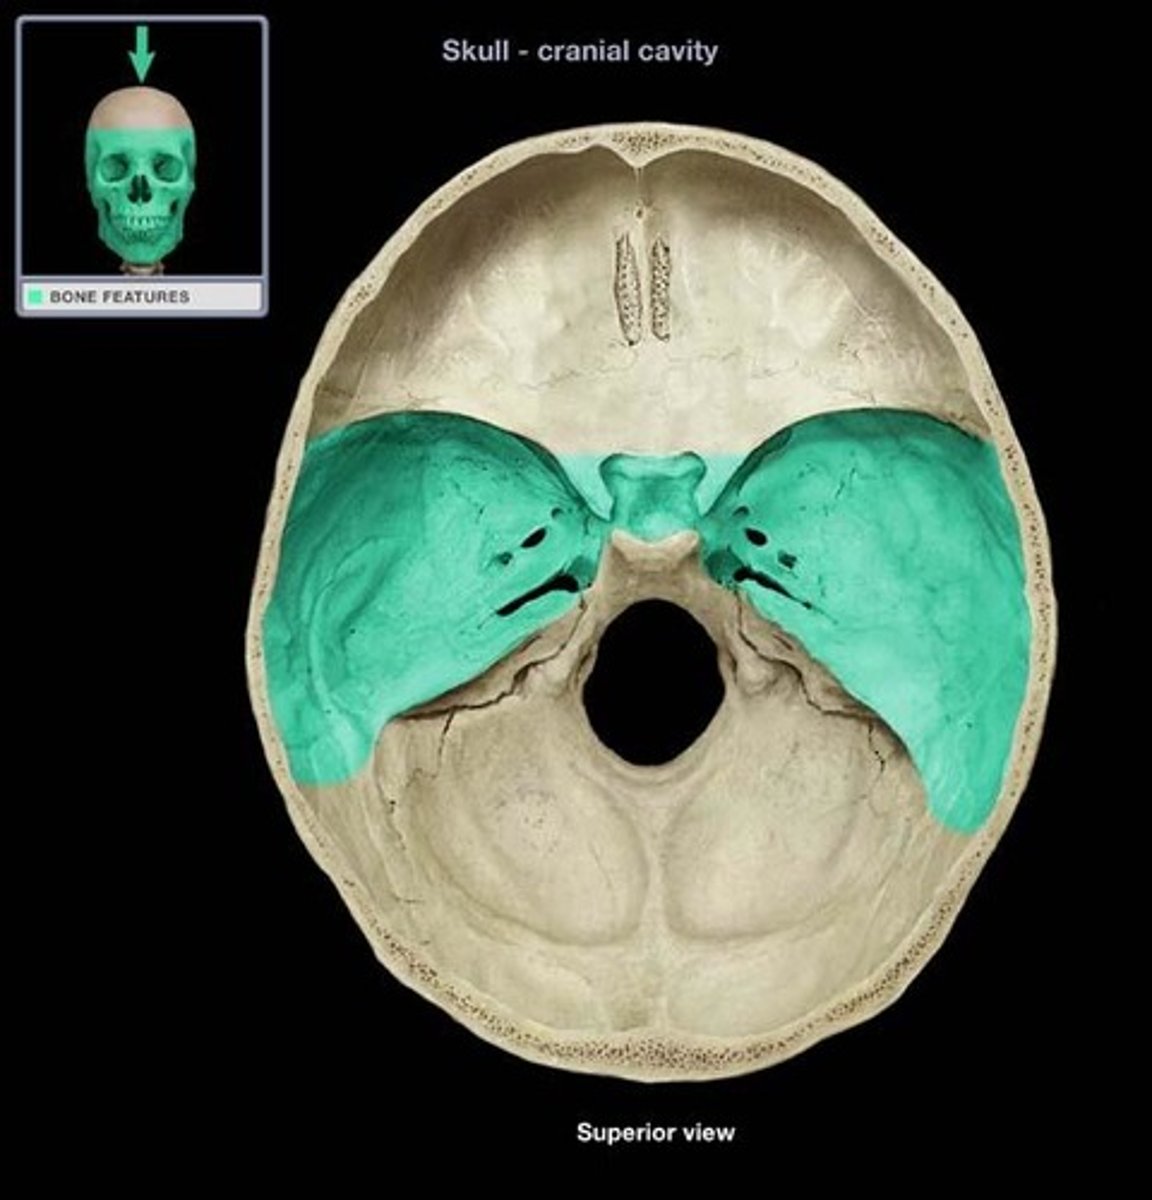

anterior cranial fossa

hypoglossal canal superior view

groove for transverse sinus

groove for superior sagittal sinus

internal occipital crest

posterior cranial fossa

sella turcica

middle cranial fossa

grooves for middle meningeal vessels